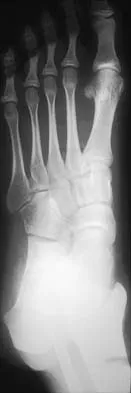

An active 47-year-old woman with rheumatoid arthritis reports forefoot pain and deformity and has difficulty with shoe wear. Examination reveals hallux valgus and claw toes. A radiograph is shown in Figure 10. What is the most appropriate surgical treatment?

Explanation

Rheumatoid arthritis commonly affects the metatarsophalangeal joints, which become destabilized with time resulting in hallux valgus and dislocated lesser claw toes. The result is metatarsalgia as the dislocated claw toes "pull" the fat pad distally. Severe hallux valgus reduces first ray load, which compounds the metatarsalgia because the load is transferred to the lesser metatarsal heads. First metatarsophalangeal arthrodesis restores weight bearing medially and corrects the painful bunion. Metatarsal head resection slackens the toe tendons to allow correction of the claw toes by whatever means necessary and decreases plantar load over the forefoot. Rheumatoid arthritis in the first metatarsophalangeal joint will continue to progress if osteotomies or a Lapidus procedure are performed. Keller resection arthroplasty increases transfer metatarsalgia and reduces push-off power during gait. Flexor-to-extensor tendon transfer of the lesser toes does not address the metatarsalgia and does not correct the dislocation of the metatarsophalangeal joint. Coughlin MJ: Arthritides, in Coughlin MJ, Mann RA (eds): Surgery of the Foot and Ankle, ed 7. St Louis, MO, Mosby, 1999, p 572.